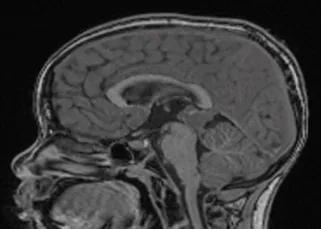

Clinical Studies Guerbet Clinical Studies Clinical Case Studies as seen in Applied Radiology Neurological and Orbital Involvement of Systemic IgG4-related Sclerosing Disease DOWNLOAD Atypical Teratoid Rhabdoid Tumor of the Oculomotor Nerve DOWNLOAD Pediatric Pineoblastoma DOWNLOAD